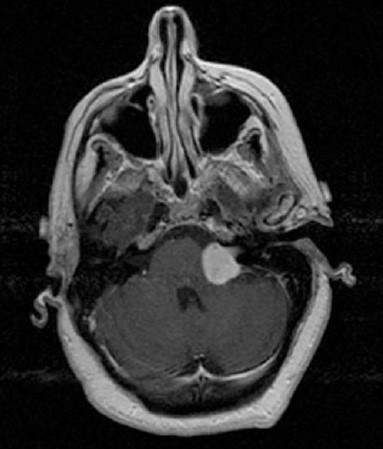

As seguintes afirmações são verdadeiras sobre o diagnóstico mais provável representado na figura abaixo, EXCETO: